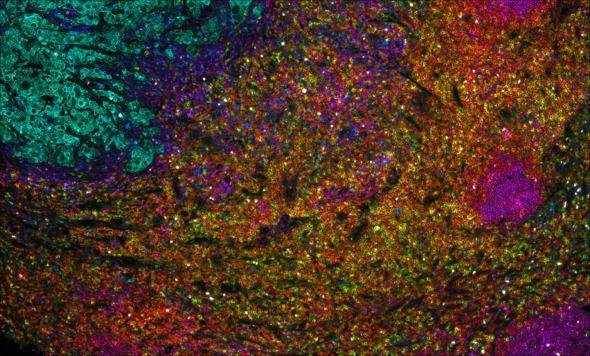

Multiplex immunofluorescence (mIF) is a powerful technique that allows researchers to simultaneously visualize and analyze multiple components of the tissue microenvironment. Multiplexing uses multiple antibodies with fluorescent detection to target specific proteins within the microenvironment, allowing researchers to create a detailed map of the various cells, proteins and their interactions. We offer both low plex and high plex options for mIF which allow you to profile tissues to determine cell phenotypes, their functional state, and cell interactions.

• Runs of 40-plex using seqIF™

• 0.23 microns/pixel

• 9×9 mm scan area can accommodate tissue sections and small tissue arrays